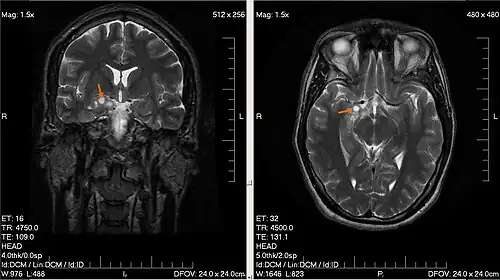

К обязательным методам обследования относятся определение активности сухожильных рефлексов, проверка тактильной и болевой чувствительности. Диагностические мероприятия могут быть расширены в зависимости от жалоб больного и с целью дифференциальной диагностики. Так, например, если больной отмечает нарушения координации, следует провести пальце-носовую пробу, проверить устойчивость в позе Ромберга. Если возникает подозрение на опухоль мозга, то больной направляется на компьютерную (КТ) или магнитно-резонансную томографию (МРТ). МРТ с контрастным усилением является «золотым стандартом» в диагностике опухолей головного мозга[6]. При обнаружении на томограмме объёмного образования решается вопрос о госпитализации больного в специализированный стационар.